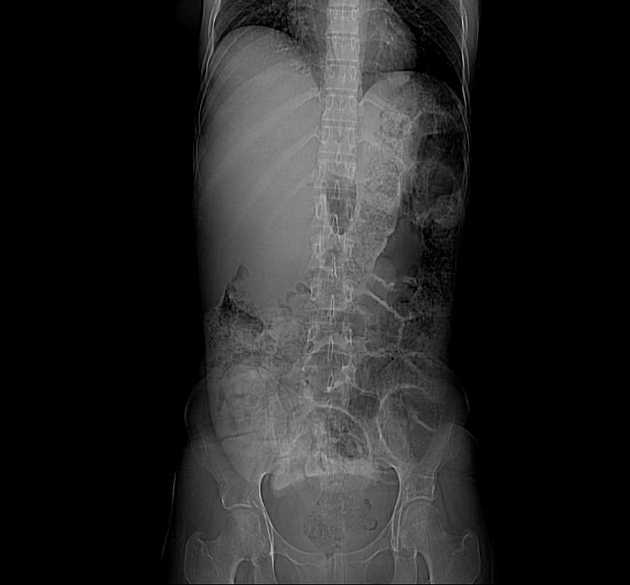

Series (9)

Coronal T2

- Có giãn dạng thoi các ống mật ngoài gan (bao gồm ống mật chủ và ống gan chung) chứa nhiều ổ giảm tín hiệu trên mọi chuỗi xung, phân bố theo trọng lực, phù hợp với hình ảnh sỏi.

- Không có giãn đường mật trong gan.

Interpretation: U nang ống mật chủ (type 1) kèm theo tổn thương IPMN nhánh bên phát hiện tình cờ (incidental side branch IPMN).

U nang ống mật chủ - type I (choledochal cyst - type I)